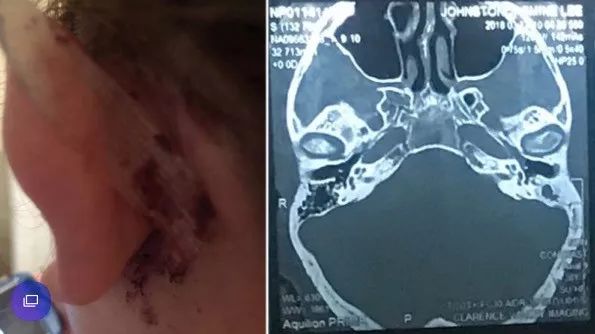

38岁的澳洲妈妈Jasmine Small和很多人一样,有用棉签掏耳朵的习惯。

当她再用棉签掏耳朵时,左耳总是感觉很疼,有时候还会有棕色的、难闻的液体流出,甚至还有血丝。

2017年底,Small换了位耳鼻喉科专家后,才发现情况已经非常严重。

CT扫描显示,Small的耳朵深处已被感染,这里非常靠近她的大脑。

很快,Small经历了一场大手术,最终保住了性命,但她的左耳已遭到永久性损害,她还需要面临一系列恢复手术,甚至佩戴助听器。